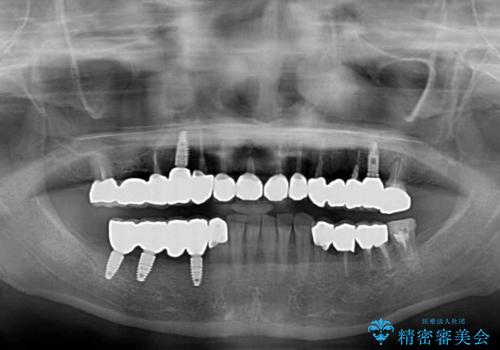

下顎右側は骨造成を併用してインプラント治療を行い、その他の奥歯もインプラントや歯周外科処置を併用して補綴治療を進め、最後に前歯部の欠けてしまったセラミッククラウンを作り替えることとしました。

海外を拠点に仕事をされているため、日本国内への入国規制の時期が重なってしまい、予定していたよりも1年ほど長い治療期間がかかってしまいました。